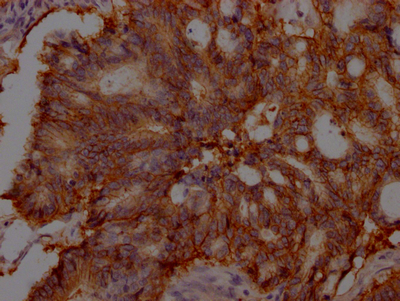

IHC image of CSB-RA439934A0HU diluted at 1:100 and staining in paraffin-embedded human colon cancer performed on a Leica BondTM system. After dewaxing and hydration, antigen retrieval was mediated by high pressure in a citrate buffer (pH 6.0). Section was blocked with 10% normal goat serum 30min at RT. Then primary antibody (1% BSA) was incubated at 4℃ overnight. The primary is detected by a Goat anti-rabbit IgG polymer labeled by HRP and visualized using 0.05% DAB.